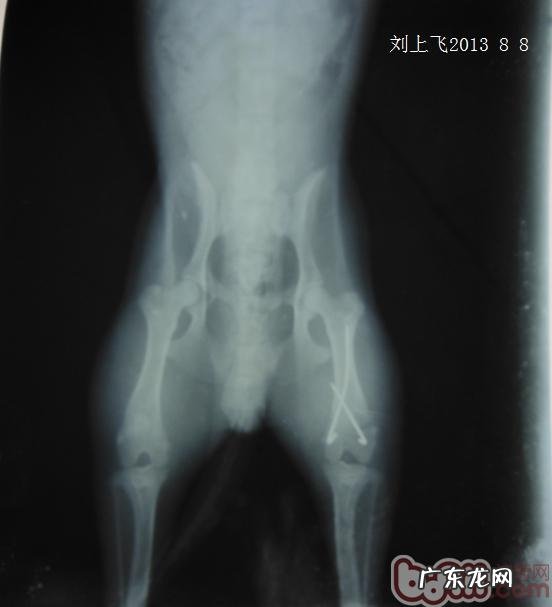

萌宠不可以单独走动,右后腿触碰有痛感,开展X光拍攝诊断 。

从图上X线可见到有后腿显著的骨裂断端 。断端贴近膝盖骨 。箭头符号所显示(孕妇左侧睡LLR)